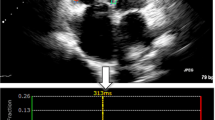

In 45 subjects (15 controls, 15 acute myocardial infarction, 15 non-ischemic dilated cardiomyopathy), end-systolic manually derived strains were compared to four CMR-FT software packages. Global radial strain (GRS), global circumferential strain (GCS) and global longitudinal strain (GLS) were determined. Intra- and inter-observer agreement and agreement between manual and CMR-FT analysis were calculated. Statistical analysis included Bland–Altman plots, intra-class correlation coefficient (ICC) and coefficient of variation (CV).

Manual contouring yielded excellent intra-observer (ICC 0.903 (GRS) to 0.995 (GCS)) and inter-observer agreement (ICC 0.915 (GRS) to 0.966 (GCS)) with CV ranging 4.7% (GCS) to 20.7% (GRS) and 12.7% (GCS) to 20.0% (GRS), for intra-observer and inter-observer agreement, respectively. Agreement between manual and CMR-FT strain values ranged from poor to excellent, with best agreement for GCS (ICC 0.857–0.935) and intermediate for GLS (ICC 0.591–0.914), while ICC values for GRS ranged widely (ICC 0.271–0.851). In particular, two software packages showed a strong trend toward systematic underestimation of myocardial strain in radial and longitudinal direction, correlating poorly to moderately with manual contouring, i.e., GRS (ICC 0.271, CV 25.2%) and GLS (ICC 0.591, CV 17.6%).